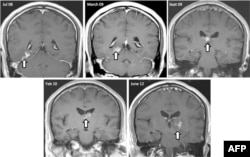

تصویر یک کرم نواری در اسکن‌های MRI مغز که چهار سال در مغز یک بیمار در بریتانیا زندگی کرده بود، ۲۰۱۴